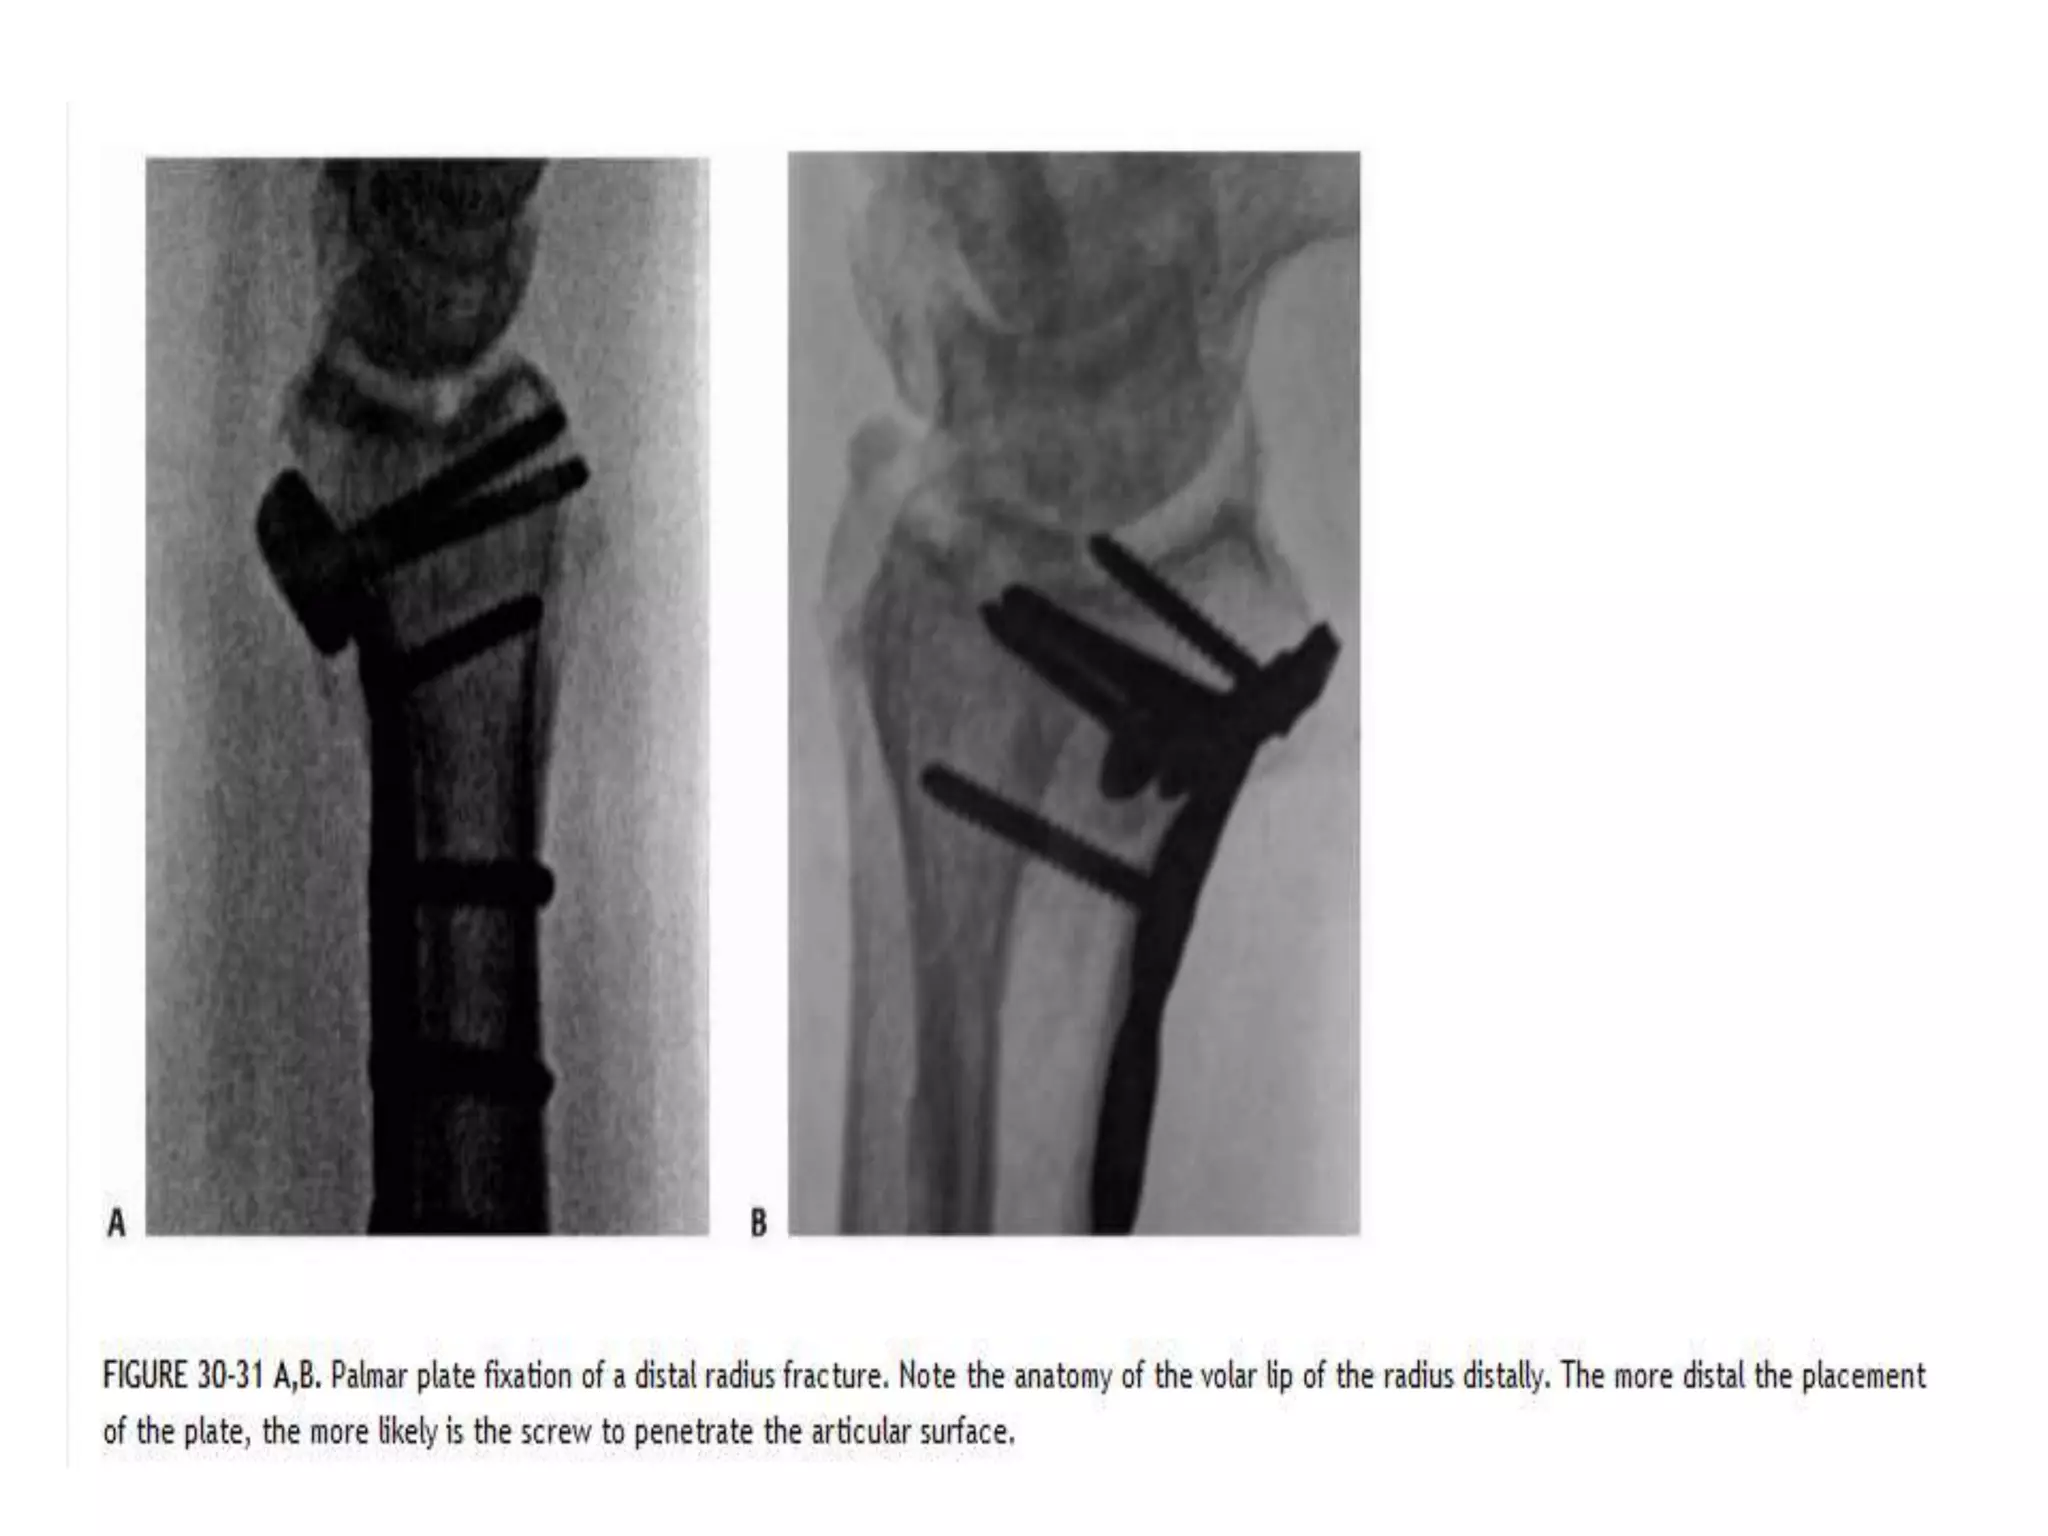

Complications

• Locking plates is the potential for articular penetration

with distal plate position on the palmar surface of the

radius

• Collapse of the fracture also can lead to joint

penetration by the distal screws especially in osteopenic

patients

• Extensor tendon problems can be caused by penetration